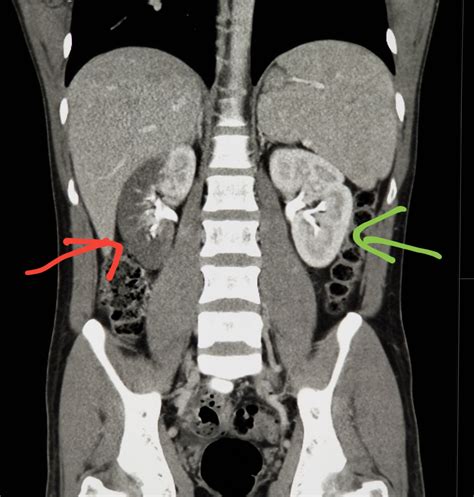

A Computed Tomography (CT) scan combines a series of X-ray images taken from different angles around your body and uses computer processing to create cross-sectional images, or "slices," of the bones, blood vessels, and soft tissues inside your body. When you undergo a CT scan for abdominal pain, the machine acts like a high-speed camera, rotating around you to generate detailed pictures that a standard X-ray simply cannot produce.

These detailed images are crucial for detecting issues that might be hidden deep within the abdominal cavity. By providing a 360-degree view, radiologists can identify inflammation, blockages, tumors, or internal injuries that require immediate medical attention.

Once the scan is complete, a radiologist—a doctor specialized in interpreting medical imaging—will analyze the images and prepare a detailed report for your primary physician or the specialist who ordered the test. This report will describe any abnormalities found, such as:

• Inflammation or Infection: Identifying conditions like appendicitis, gallbladder inflammation, or diverticulitis.

• Organ Enlargement: Detecting issues with the liver, spleen, or kidneys.

• Obstructions: Finding blockages in the intestines caused by scar tissue, tumors, or hernia.

• Fluid Collections: Spotting abscesses or internal bleeding.